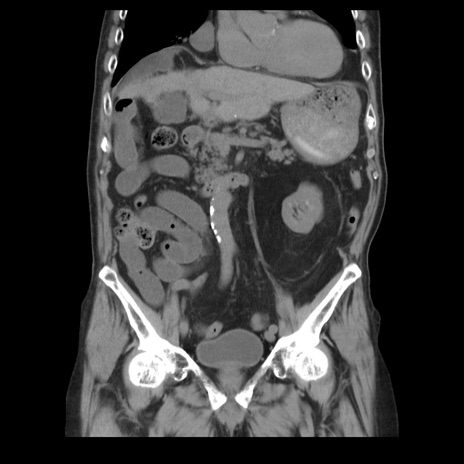

症例21(冠状断像)

【症例】70歳代男性

【主訴】腹痛

【現病歴】肝硬変・肝細胞癌にてかかりつけの方。約9時間前に食後より腹痛出現。症状が徐々に増悪し、嘔吐出現したため来院。

【既往歴】肝硬変、肝細胞癌(RFA、TACE後)

【身体所見】意識清明、表情苦悶様、BT 36℃、BP 129/78mmHg、P 88bpm、SpO2 97%(RA)、右上腹部から心窩部にかけて圧痛あり、反跳痛なし、筋性防御あり。

【データ】WBC 5800、CRP 0.16